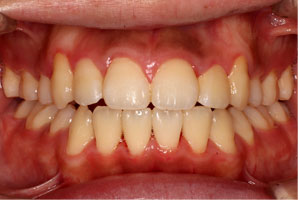

こちらの初診(男性)の患者さんは、開咬合 / 叢生歯列の症状がありました。

1期治療 8歳9ヶ月 2期治療 12歳4ヶ月から治療を開始し、1期治療 7ヶ月 2期治療 2年5ヶ月の間、スタンダードエッジワイズ法(与五沢エッジワイズシステム)を用い矯正治療を行いました。

| 症例分類 | 開咬合 / 叢生歯列 / 偏位咬合 | |||||||||||||||||||||||||||||||||||||||||||||||||||||||||||